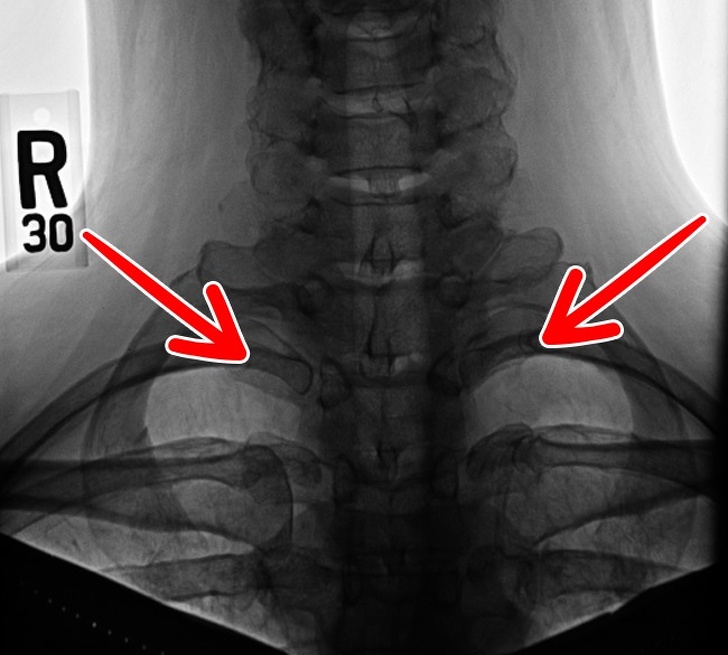

4. Шийні ребра

Набором додаткових шийних ребер, які ми, можливо, успадкували від рептилій, має менше 1 % населення Землі. У деяких людей шийні ребра можуть бути лише ліворуч або праворуч, в той час як в інших — з обох сторін. Ці зайві кісткові пластини часто бувають причиною неврологічних проблем і здавлення підключичної артерії.